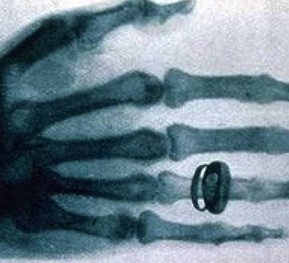

X光安檢機?,又叫安檢機。是地鐵、車站、機場等的行李安檢設備。它的原理也很簡單,就是利用X射線能穿透物質的能力,對各種物質照射穿透,以此識別行李中包含的各種物體。